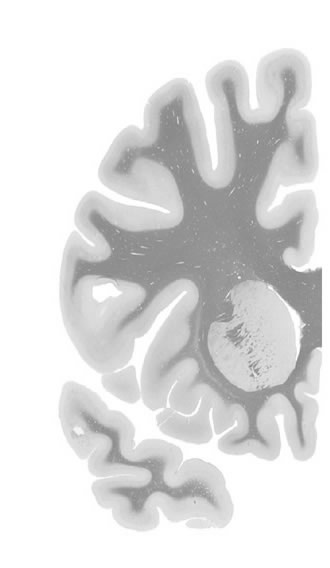

Frontal sections (Nissl) from the Atlas Brain:

Slice

Macroscopy

Slice ID:

r2-0545

Plate NR:

10-11

Position:

-18,5 mm